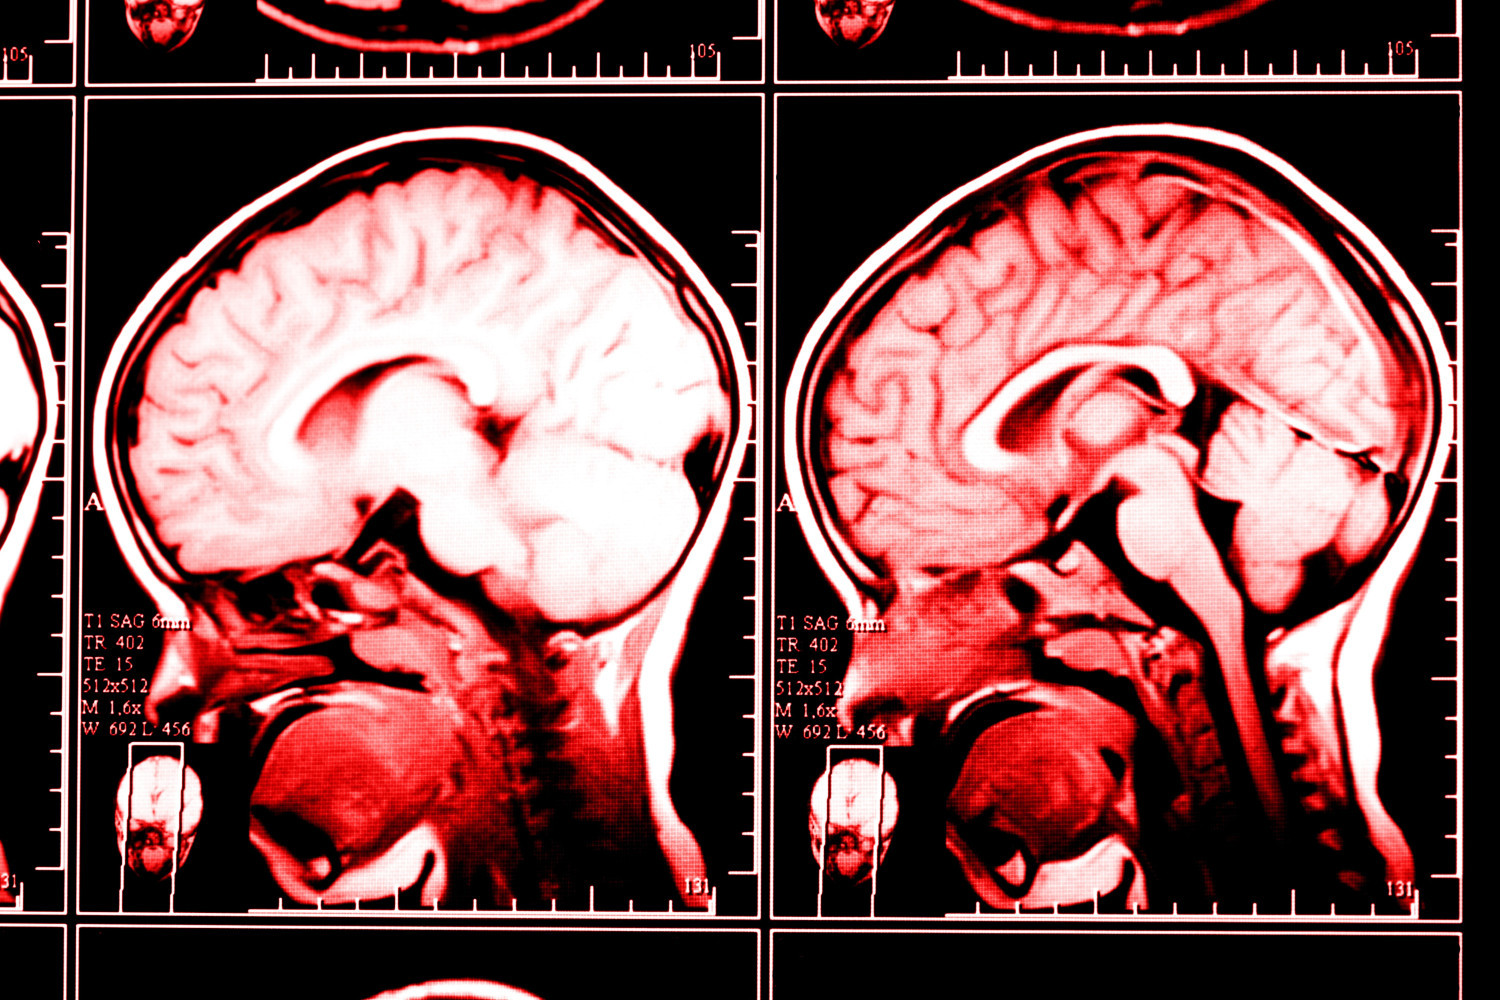

Ранняя реверсия антикоагулянтной терапии улучшала выживаемость при внутримозговом кровоизлиянии

Ученые выяснили, связано ли раннее введение реверсивных агентов с улучшением исходов у пациентов с внутримозговым кровоизлиянием, вызванным применением антикоагулянтов. Результаты исследования опубликованы в JAMA Neurology.

Анализ показал, что введение реверсивных агентов в течение 60 минут после поступления пациента в больницу снижало риск смерти на 17%. Наиболее значимое снижение смертности наблюдалось у пациентов, которые принимали варфарин. Также при ранней реверсии антикоагулянтной терапии вероятность попадания пациента с внутримозговым кровоизлиянием в хоспис уменьшалась на 18%.

| Анализировали данные 9492 пациентов с внутримозговым кровоизлиянием, связанным с приемом антикоагулянтов. Средний возраст участников составил 77 лет. Из них 7469 (78,7%) получили реверсивное вмешательство. |

Первичной переменной воздействия было время «от двери до иглы», определяемое как время от прибытия в больницу до начала введения реверсивного агента. В качестве основного результата оценивали показатели внутрибольничной смертности и перевод пациентов в хоспис.